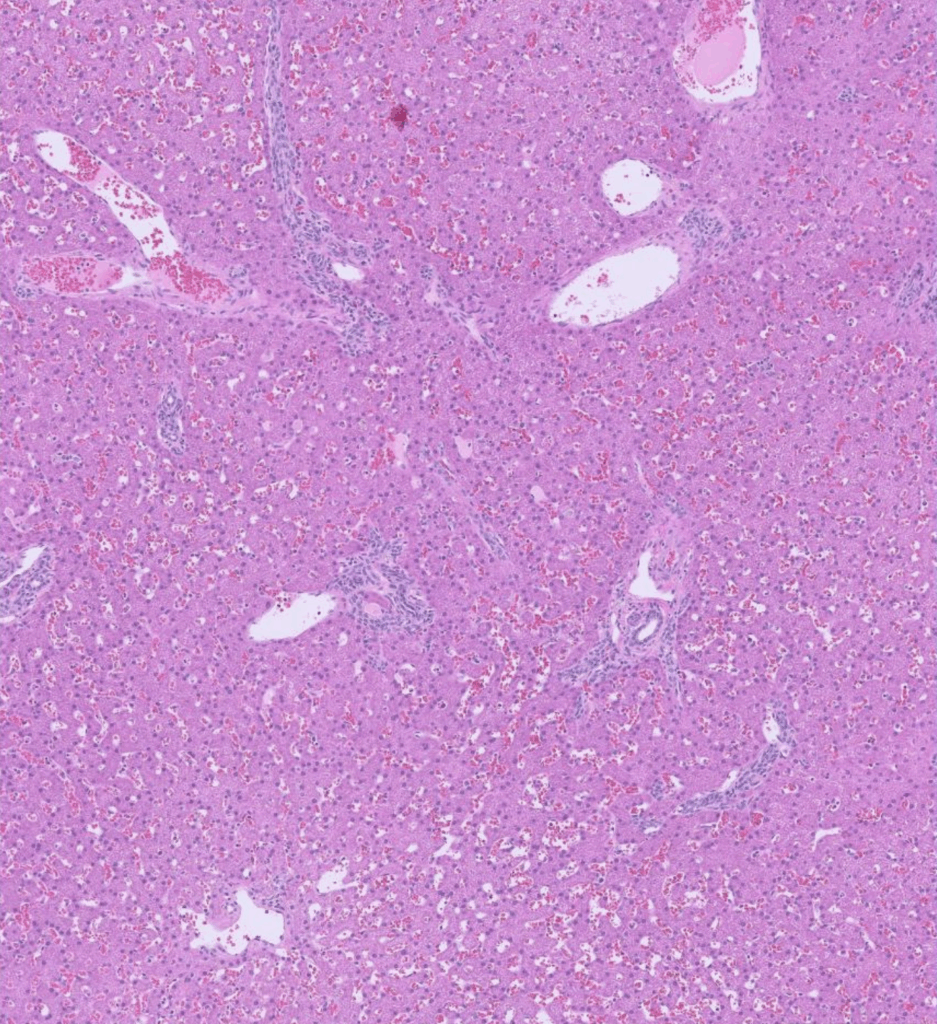

Excisional Liver Biopsy

Liver Biopsy:

Liver: Lobular hypoplasia, diffuse, chronic, moderate, with hepatocellular atrophy, arteriolar reduplication, and mild biliary hyperplasia. The vascular changes in this liver represent a stereotypic response to insufficient portal blood supply resulting from either a congenital shunt, portal vein hypoplasia (microvascular dysplasia), or acquired portal hypertension due to cirrhosis or extrahepatic causes.